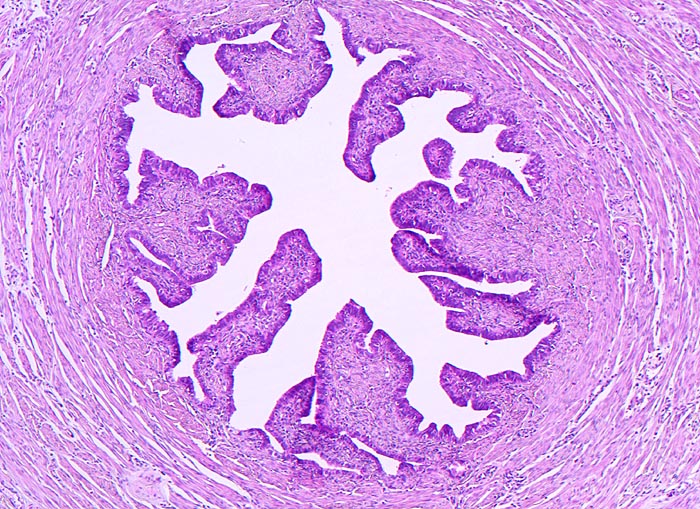

PathoPic ID 4451 - Tuba uterina

Tuba uterina

Normalbefund

Genitalorgane, weiblich

Tumorfreie Tube. Prominente Schleimhautfalten und sternförmiges Lumen. Aussen die zirkulär angeordnete glatte Muskelschicht.

Bilateraler Ovarialtumor als Zufallsbefund bei einer gynäkologischen Kontrolluntersuchung.

Histologie

50